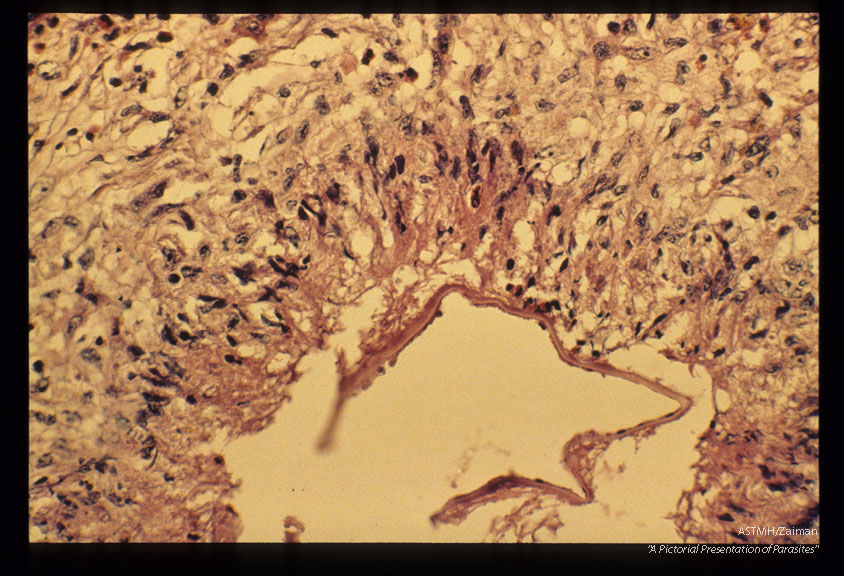

Gross and microscopic photos of human liver from Minnesota where about one half of the red foxes are infected.

Echinococcus multilocularis

Description: Gross and microscopic photos of human liver from Minnesota where about one half of the red foxes are infected.